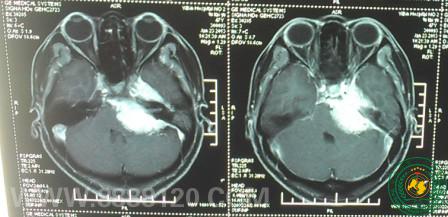

我科成功完成左侧中后颅窝肿瘤切除一例

我科成功完成左侧中后颅窝肿瘤切除一例3911